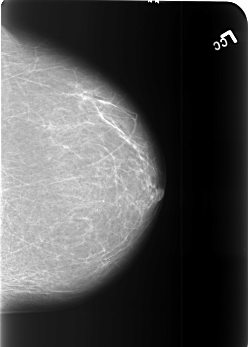

B_3451_1.LEFT_MLO

B_3451_1.LEFT_CC

LEFT_MLO LINES 5584 PIXELS_PER_LINE 4032 BITS_PER_PIXEL 12 RESOLUTION 50 NON_OVERLAY

LEFT_CC LINES 5544 PIXELS_PER_LINE 3968 BITS_PER_PIXEL 12 RESOLUTION 50 NON_OVERLAY